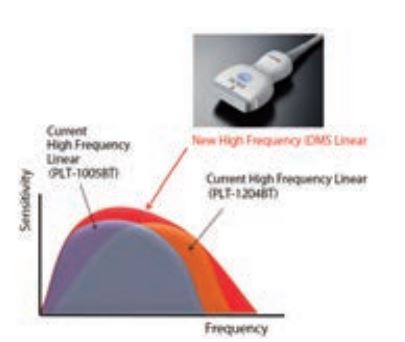

Завдяки використанню інноваційної технології формування пучка iBeam, передової технології інтелектуального динамічного мікрозрізу (iDMS) та новітніх компонентів датчика, для серії AplioTM i були розроблені два нових високочастотних лінійних датчика. Ці технології створюють більш чіткий, тонкий і рівномірний ультразвуковий промінь. Зображення у відтінках сірого

Ультраширокосмуговий високочастотний лінійний датчик охоплює частотний діапазон, який зазвичай покривається двома попередніми лінійними датчиками (1005BT і 1204BT), що поєднує оптимальну роздільну здатність і глибину проникнення в одному датчику. Завдяки цьому датчику 2-в-1 можна більш ефективно здійснювати менеджмент датчиків.

Мал 1. Надширокосмуговий високочастотний лінійний датчик